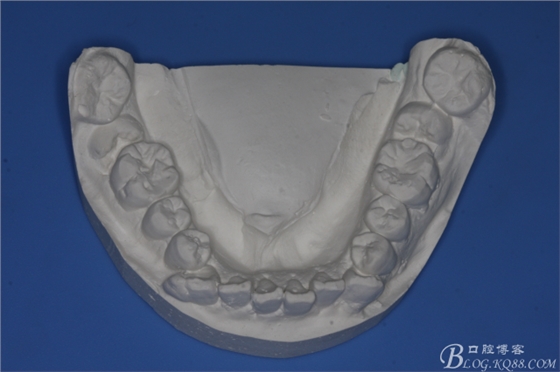

圖1.術(shù)前的正畸科病例:

圖2.術(shù)前的正畸工作模型:47低位近中阻生、37近中中位阻生